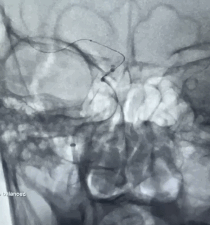

Tarvos微导丝携微导管到位。

动脉长鞘怎么置入有励可说|Locaste 088励楷长鞘及Tarvos微导丝在右侧大脑中动脉M2段取栓术中的应用_https://www.jmylbn.com_新闻资讯_第14张

动脉长鞘怎么置入有励可说|Locaste 088励楷长鞘及Tarvos微导丝在右侧大脑中动脉M2段取栓术中的应用_https://www.jmylbn.com_新闻资讯_第15张

动脉长鞘怎么置入有励可说|Locaste 088励楷长鞘及Tarvos微导丝在右侧大脑中动脉M2段取栓术中的应用_https://www.jmylbn.com_新闻资讯_第16张

动脉长鞘怎么置入有励可说|Locaste 088励楷长鞘及Tarvos微导丝在右侧大脑中动脉M2段取栓术中的应用_https://www.jmylbn.com_新闻资讯_第17张

支架释放,采用SWIM技术取栓。